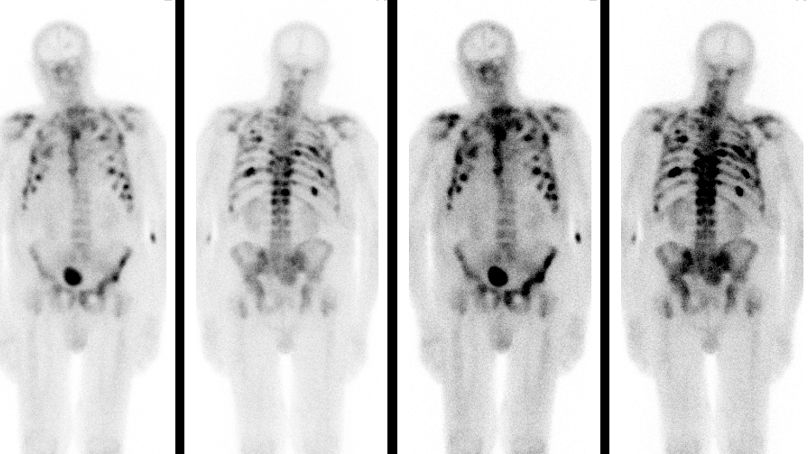

77-jähriger Mann mit Rückenschmerzen. PSA 1700! Im

Knochenszintigramm Hinweis auf diffuse Knochenmetastasierung.![]() | ||||||||||||||||||||